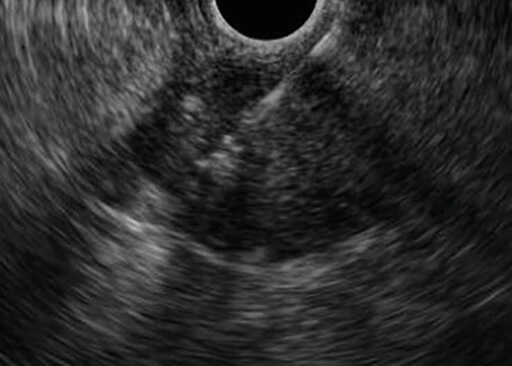

Εικόνα 3: Υπερηχογενές λίπωµα στοµάχου

Εικόνα 3